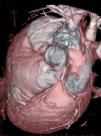

Se muestran las imágenes del árbol coronario que permiten descartar anomalías en esta localización. La figura 1 muestra una proyección axial de máxima intensidad (MIP) de la salida de las arterias coronarias. La figura 2 es una proyección coronal de máxima intensidad (MIP) de la arteria coronaria derecha similar a la proyección oblicua anterior derecha de la angiografía. Las figuras 3 y 4 son reconstrucciones en volume rendering en proyección oblicua anterior izquierda del tronco coronario izquierdo y su bifurcación y de la base del corazón, en la que se visualiza la salida del tronco coronario izquierdo. Se han retirado las venas pulmonares izquierdas. En la estación de trabajo, mediante el análisis avanzado de vasos se puede visualizar un vaso tortuoso o de trayecto curvo en un solo plano tomográfico permitiendo una cuantificación de la lesiones estenóticas. El estudio no detectó anomalía en la anatomía ni estenosis coronaria significativa en el paciente.

Figura 3. Reconstrucción en volume rendering en proyección lateral izquierda del tronco coronario izquierdo y su bifurcación. ADA: arteria coronaria derecha; TCI: tronco coronario izquierdo; ACX: arteria circunfleja.